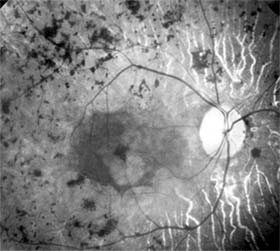

Retinitis Pigmentosa

Retinitis pigmentosa is a group of hereditary retinal degenerations characterized by progressive dysfunction of the photoreceptors and associated with progressive cell loss and eventual atrophy of several retinal layers. The typical form of this disease can be inherited as an autosomal recessive, autosomal dominant, or X-linked recessive trait; one-third of cases will have a negative family history. The hallmark symptoms of retinitis pigmentosa are night blindness (nyctalopia) and gradually progressive peripheral visual field loss. The most characteristic ophthalmoscopic findings are narrowing of the retinal arterioles, mottling of the retinal pigment epithelium, and peripheral retinal pigment clumping, referred to as "bone-spicule formation" (Figure 10-19). While retinitis pigmentosa is a generalized photoreceptor disorder, in most cases rod function is more severely affected, leading to subjective sensations associated with poor scotopic function. The electroretinogram usually shows either markedly reduced or absent retinal function; the electro-oculogram lacks the usual light rise. The fundus appearance of retinitis pigmentosa may be mimicked by several disorders, including chorioretinitis, trauma, vascular occlusion, and resolved retinal detachment.

Figure 10-19

Figure 10-19: Retinitis pigmentosa with arteriolar narrowing and peripheral retinal pigment clumping.

The effects of supplemental vitamins on the progression of retinitis pigmentosa require further study before treatment recommendations can be made. Patients with the disease benefit from genetic counseling and appropriate referral to agencies that provide services to the visually impaired.